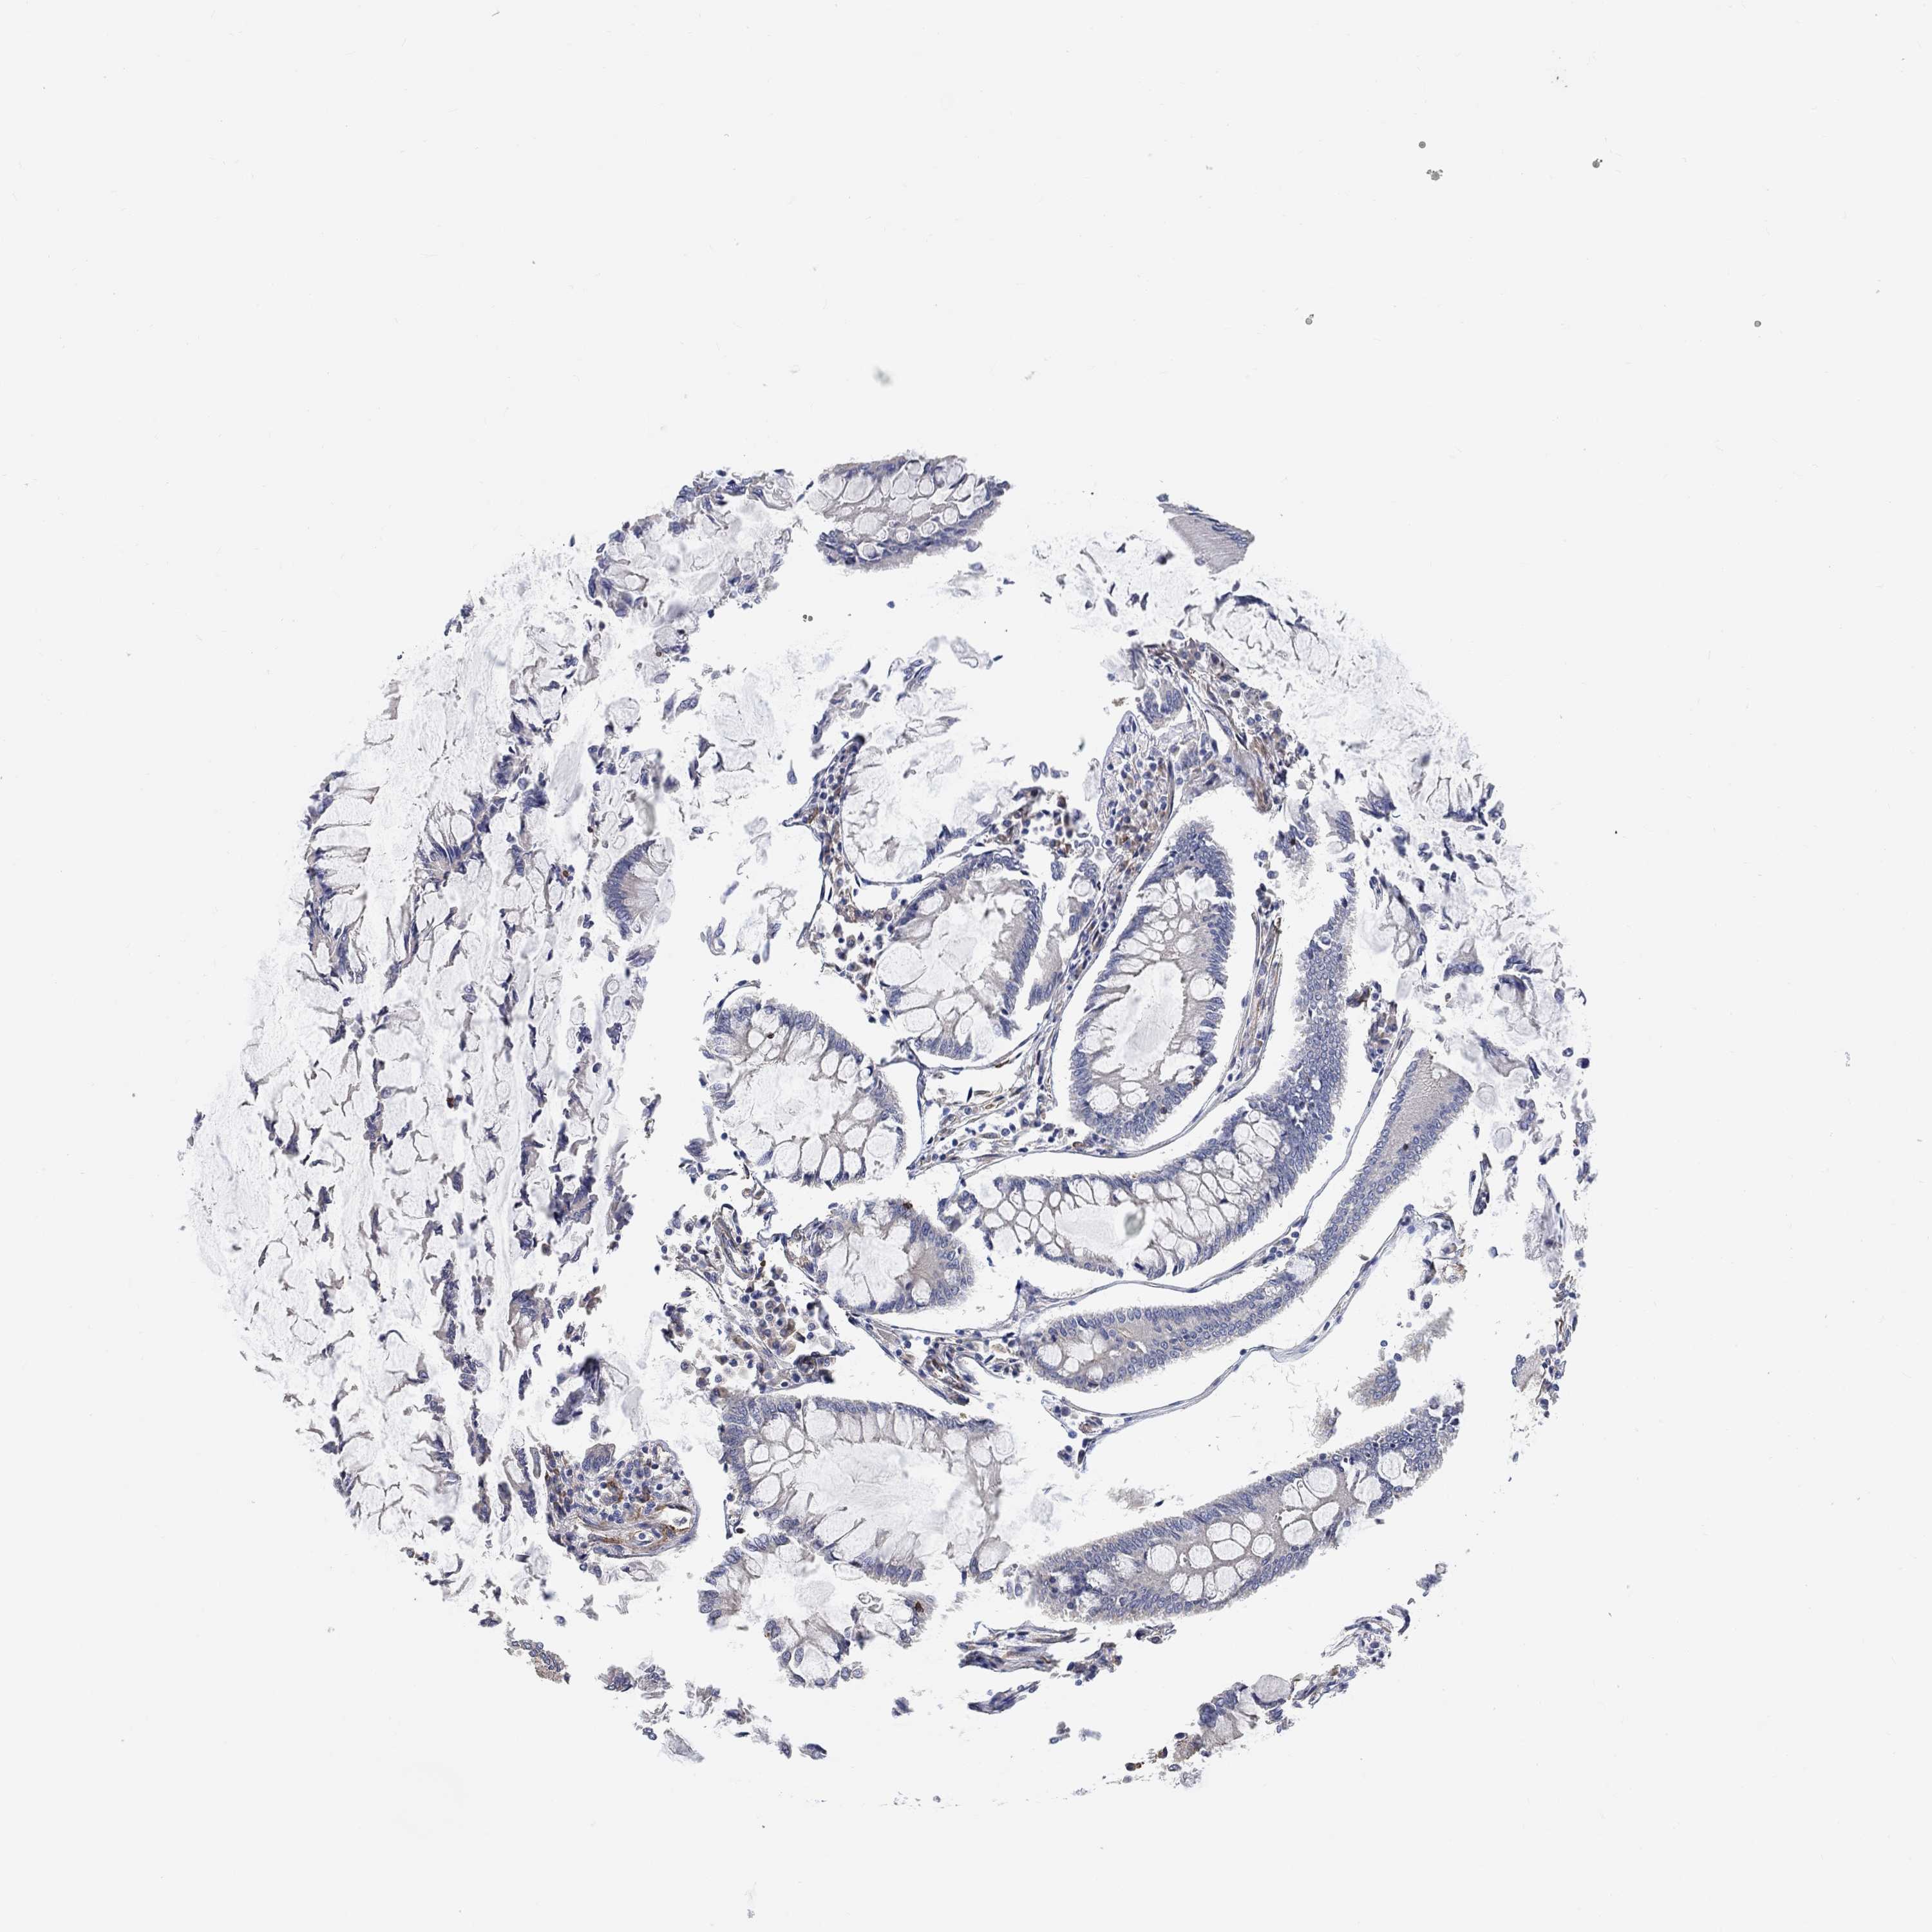

CANCER COLORECTAL CANCER Show tissue menu

Colorectal cancer

Human cancer

Colon adenocarcinoma